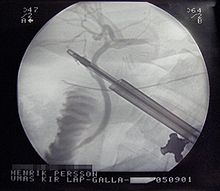

X-ray during laparoscopic cholecystectomy

Surgery

For most people with acute cholecystitis, the treatment of choice is surgical removal of the gallbladder, laparoscopic cholecystectomy.[31] Laparoscopic cholecystectomy is performed using several small incisions located at various points across the abdomen. Several studies have demonstrated the superiority of laparoscopic cholecystectomy when compared to open cholecystectomy (using a large incision in the right upper abdomen under the rib cage). People undergoing laparoscopic surgery report less incisional pain postoperatively as well as having fewer long term complications and less disability following the surgery.[32][33] Additionally, laparoscopic surgery is associated with a lower rate of surgical site infection.[34]

During the days prior to laparoscopic surgery, studies showed that outcomes were better following early removal of the gallbladder, preferably within the first week.[35] Early laparoscopic cholecystectomy (within 7 days of visiting a doctor with symptoms) as compared to delayed treatment (more than 6 weeks) may result in shorter hospital stays and a decreased risk of requiring an emergency procedure.[36] There is no difference in terms of negative outcomes including bile duct injury or conversion to open cholecystectomy.[36] For early cholecystectomy, the most common reason for conversion to open surgery is inflammation that hides Calot's triangle. For delayed surgery, the most common reason was fibrotic adhesions.[36]